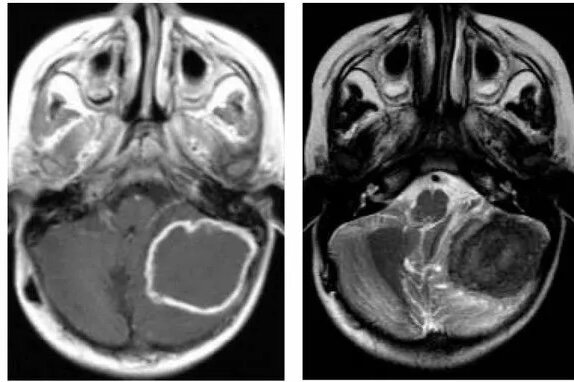

Гумма головного мозга – встречается редко, похожа на экстрамедулярную опухоль по клинике